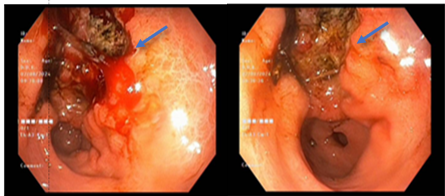

- Nội soi thực quản - dạ dày - tá tràng: Dạ dày dịch nâu đen. Hang vị và bờ cong nhỏ có ổ loét sùi lớn, đáy gồ ghề xuất huyết, bờ gồ cao không đều

Hình 1. Hình ảnh nội soi dạ dày - thực quản - tá tràng: Hình ảnh vùng hang vị có ổ loét sùi chảy máu, đáy gồ ghề, bờ không đều (mũi tên xanh dương)